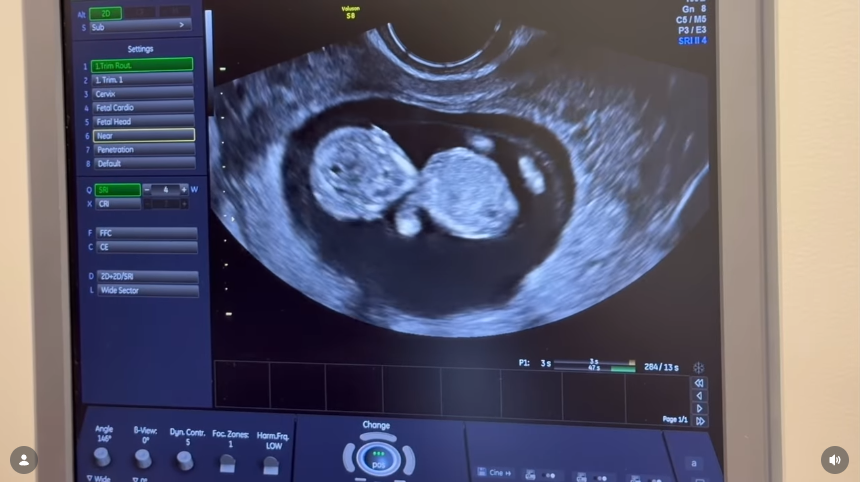

W krótkim filmie widać Wersow z zaokrąglonym brzuchem i córkę Friza i Wersow Maję, która trzyma w ręku zdjęcie USG.